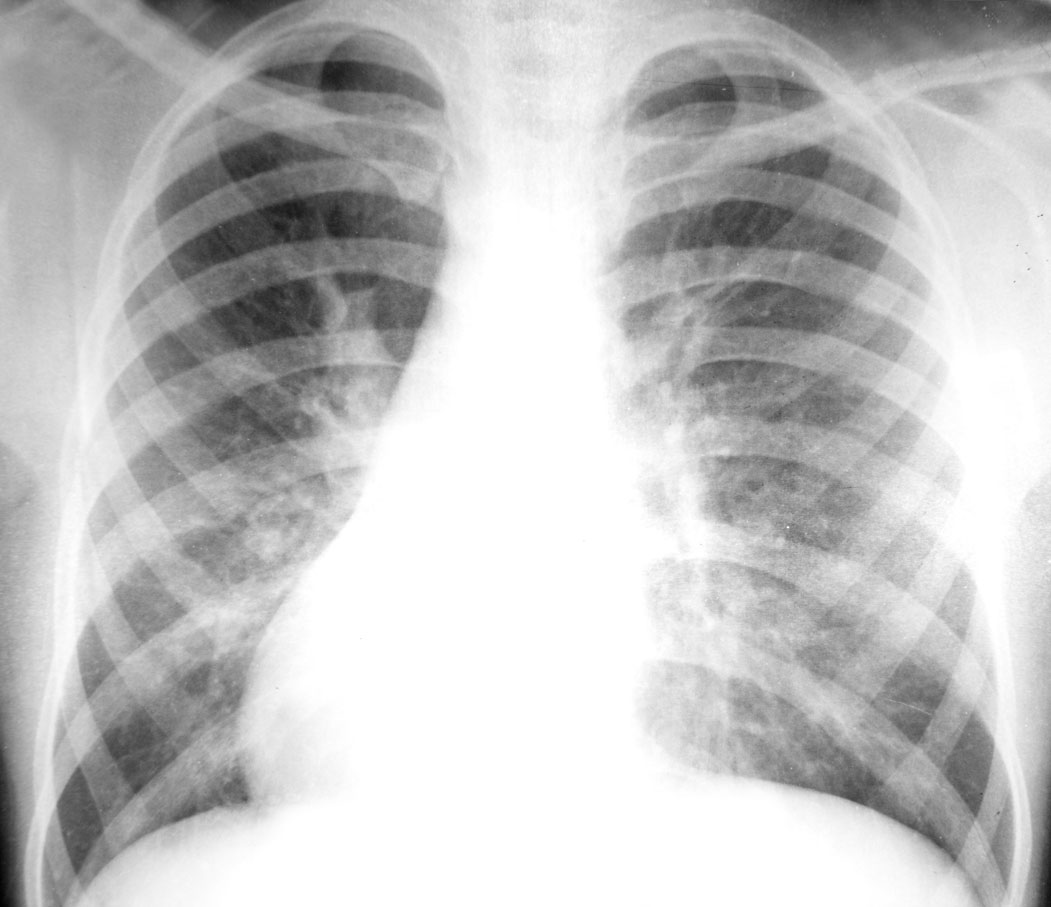

Special Topics in Tuberculosis Management